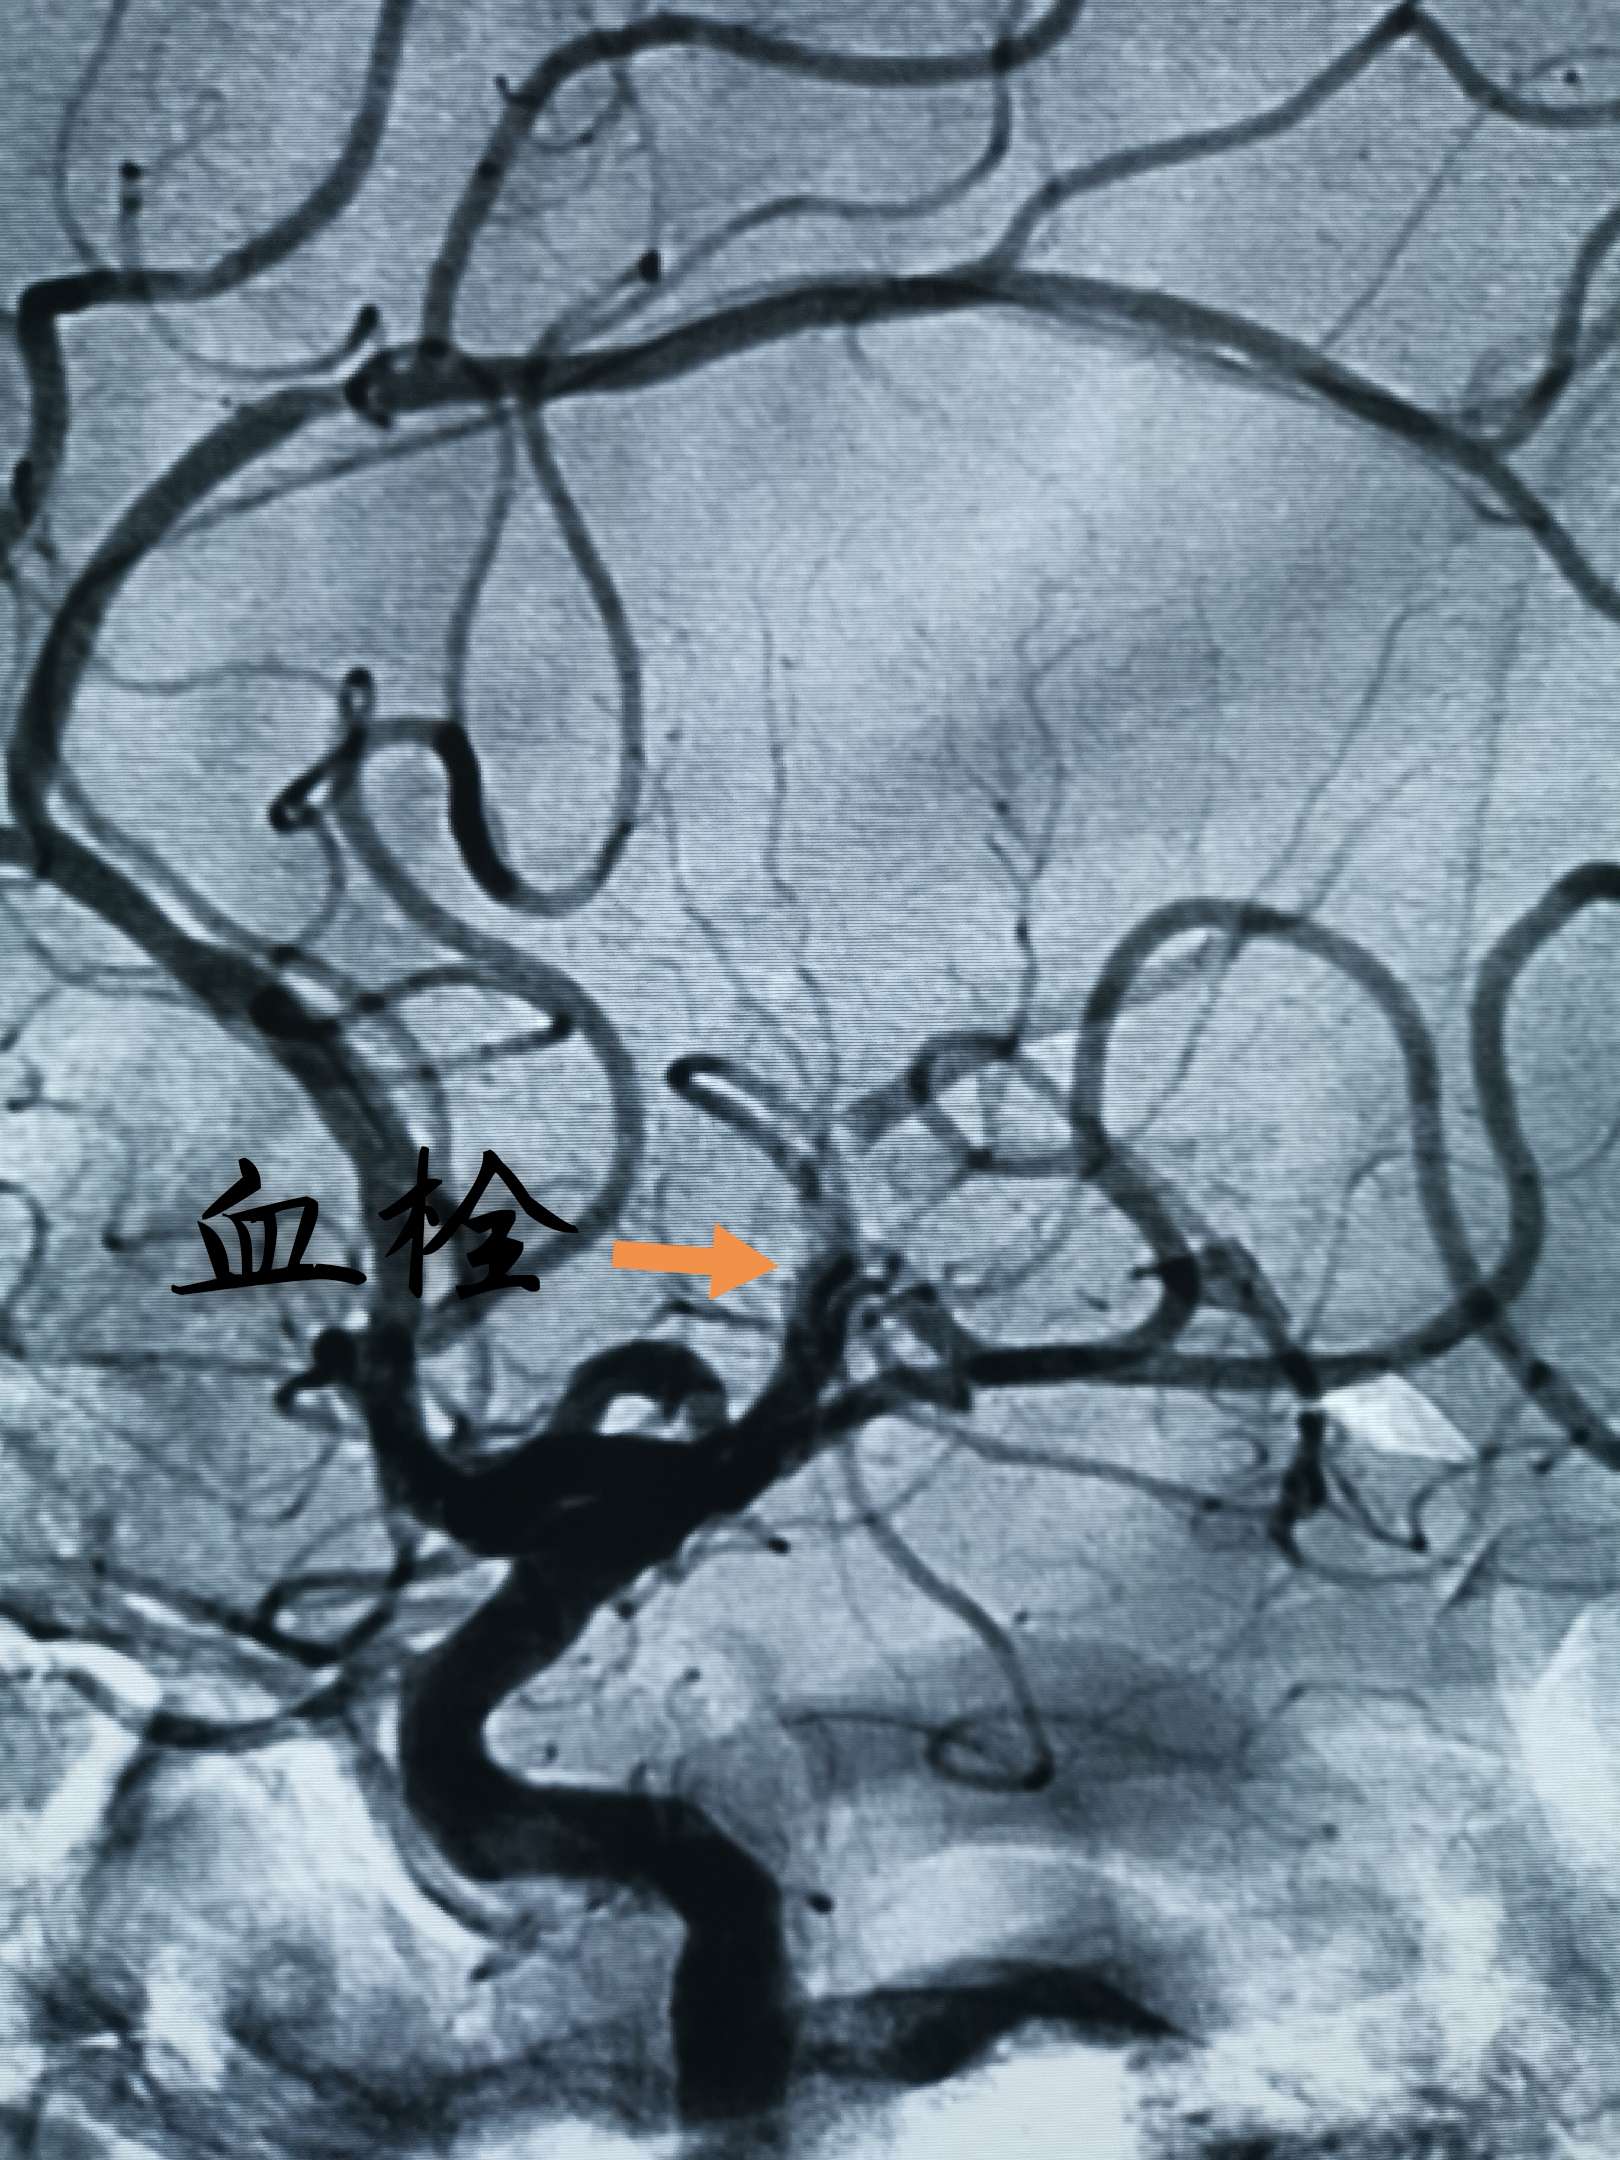

快速转运并完成DSA,发现右侧大脑中动脉M2、M3分叉处血栓,两大分支血流缓慢

Guiding内造影发现M3分支不显影